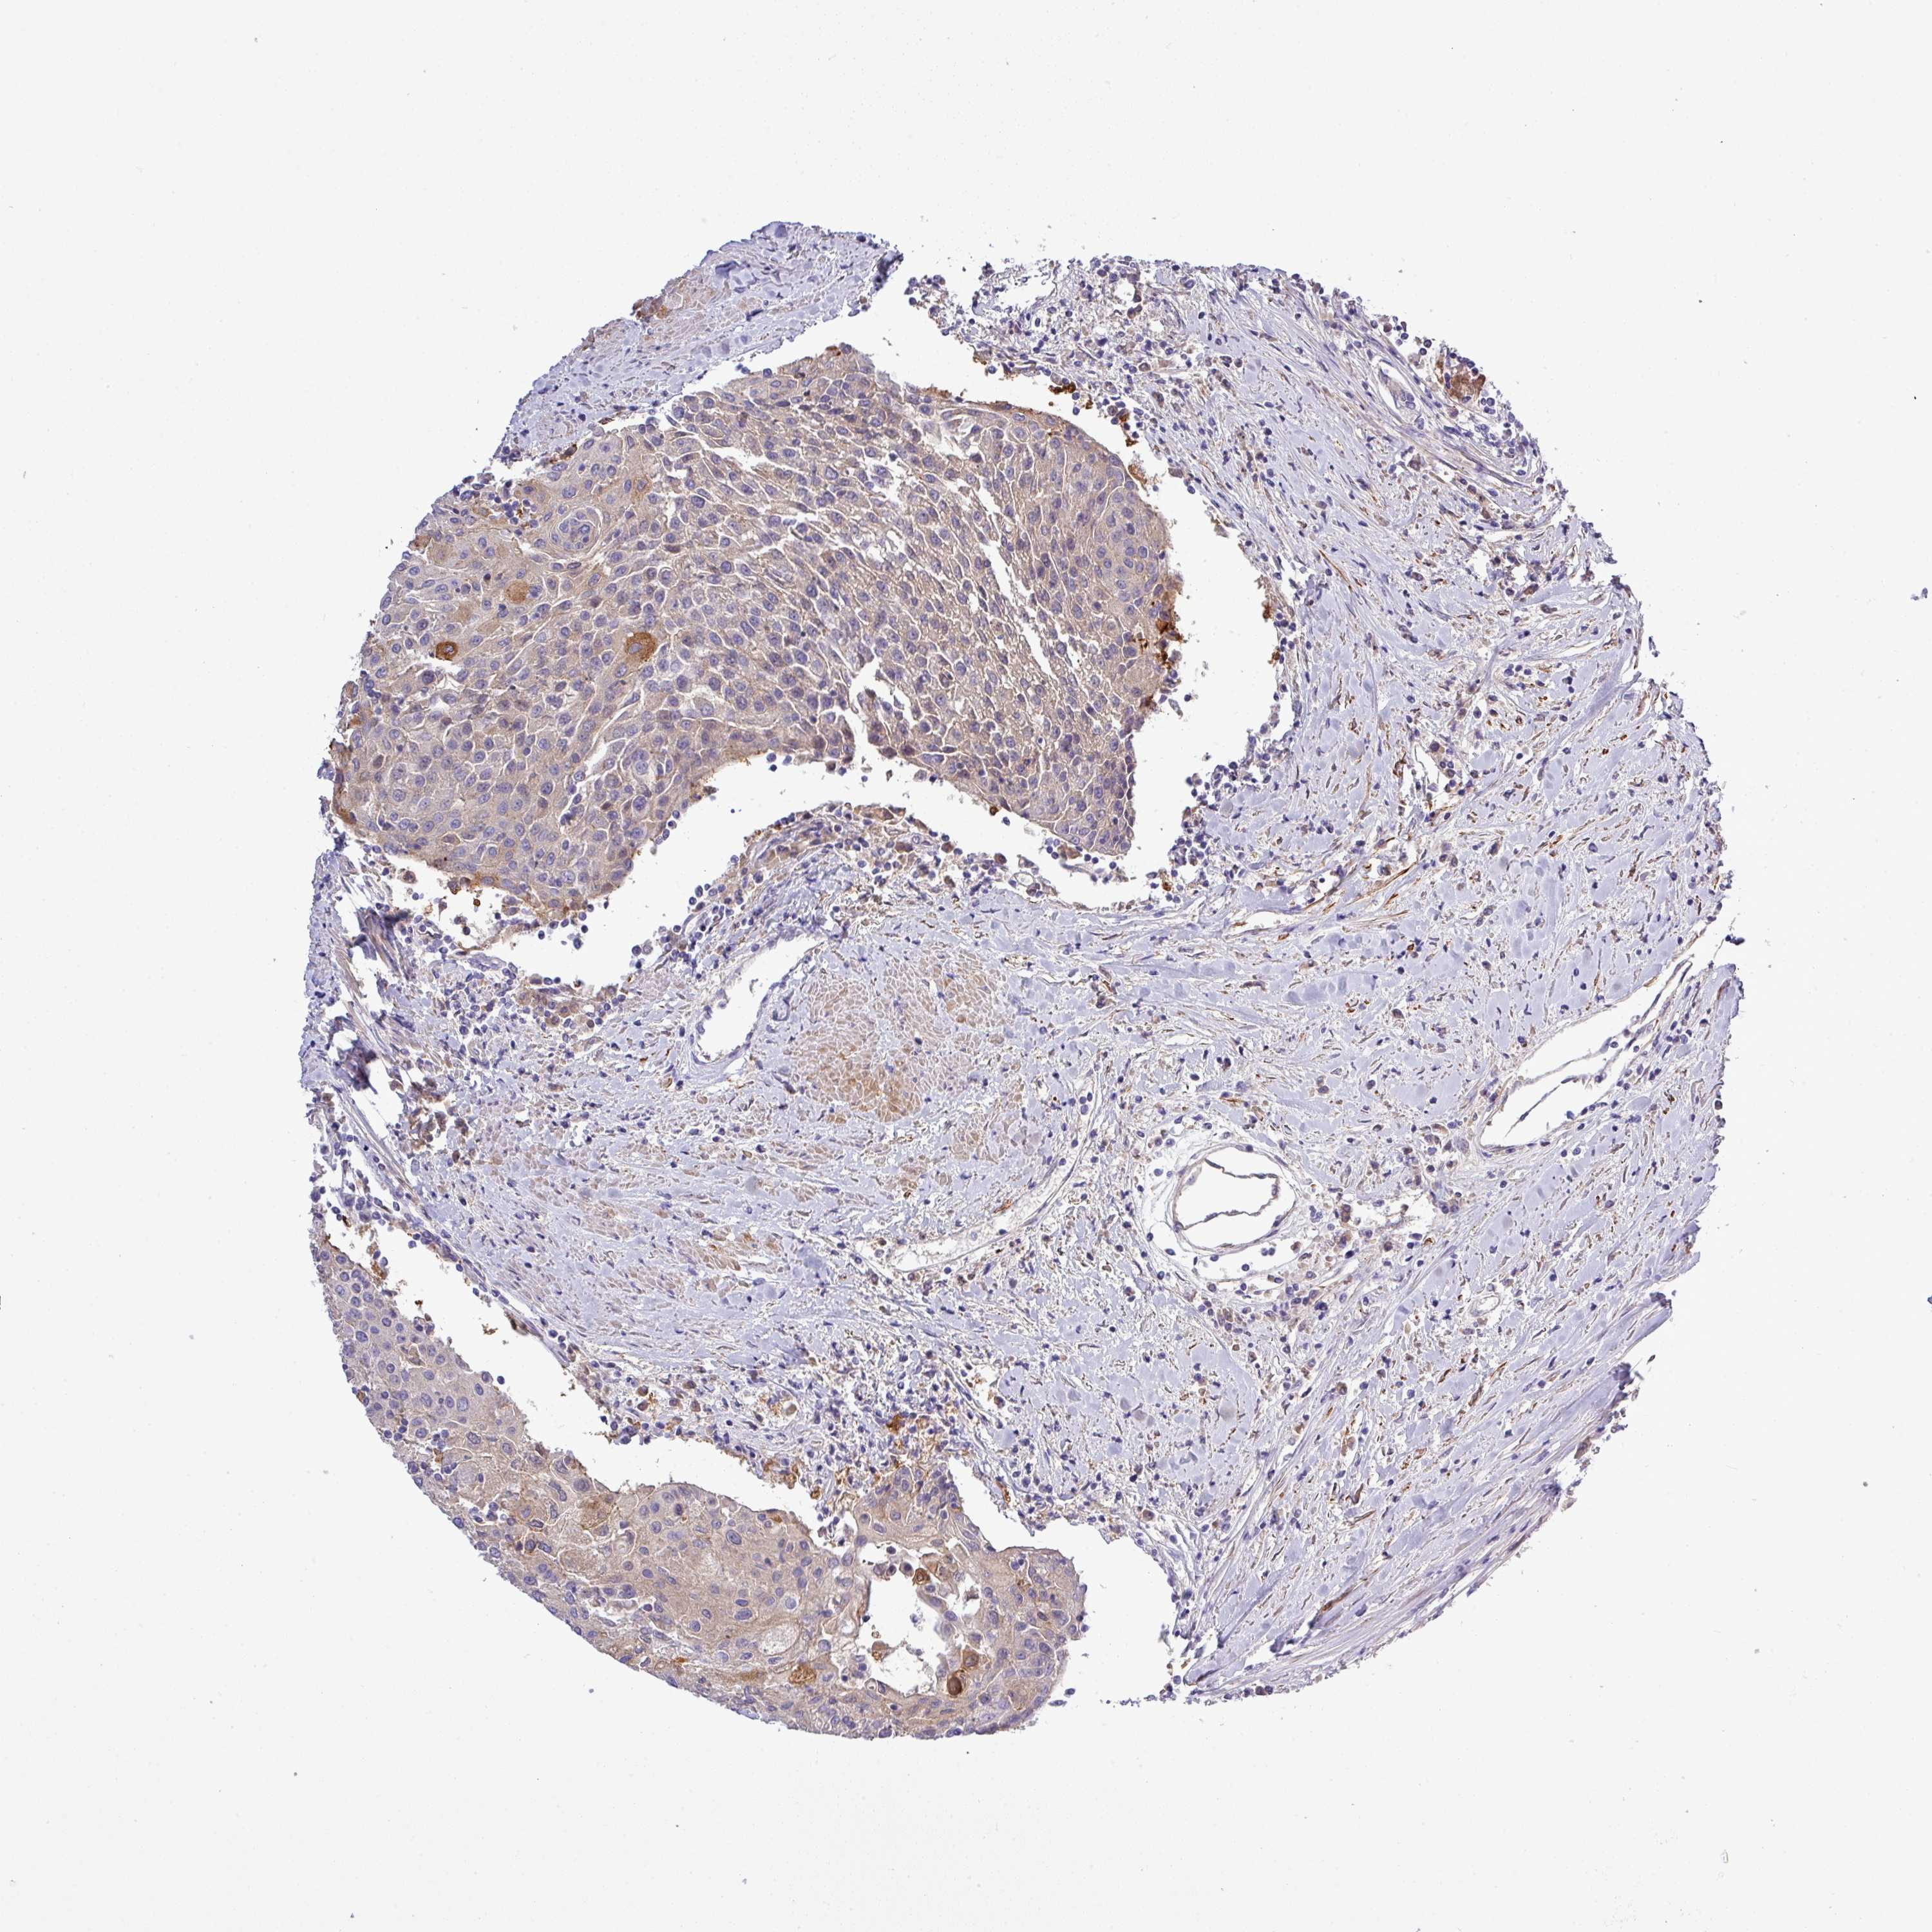

UROTHELIAL CANCER - Protein expressioni

A mouse-over function shows sample information and annotation data. Click on an image to view it in a full screen mode. Samples can be filtered based on level of antibody staining by selecting one or several of the following categories: high, medium, low and not detected. The assay and annotation is described here.

Note that samples used for immunohistochemistry by the Human Protein Atlas do not correspond to samples in the TCGA dataset.

Antibody stainingi

Antibody staining in the annotated cell types in the current human tissue is reported as not detected, low, medium, or high, based on conventional immunohistochemistry profiling in selected tissues. This score is based on the combination of the staining intensity and fraction of stained cells.

Each image is clickable and will lead to virtual microscopy that enables deeper exploration of all samples and also displays staining intensity scores, fraction scores and subcellular localization as well as patient and tissue information for each sample.

Antibody HPA041551

Antibody CAB009733

Urothelial carcinoma, Low grade

Urothelial carcinoma, High grade